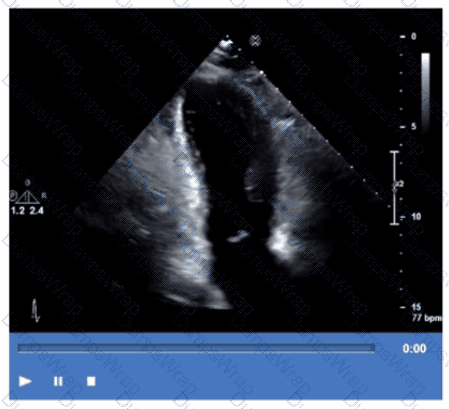

Which finding is demonstrated in this video?

CExplanation:

The echocardiographic video shows a prosthetic ring-like structure attached to the mitral annulus with preserved native leaflet motion, consistent with an annuloplasty ring repair. Annuloplasty rings are used to reduce the mitral annulus size and improve leaflet coaptation in mitral regurgitation without replacing the valve.

Bioprosthetic or mechanical valve replacements would show distinctly different echogenic valve structures with leaflet or disc motion replacing the native valve. Extensive calcification of a native valve appears as echogenic, thickened leaflets without a discrete ring.

This is described in the "Textbook of Clinical Echocardiography, 6e", Chapter on Mitral Valve Repair Techniques【20:400-405†Textbook of Clinical Echocardiography】.